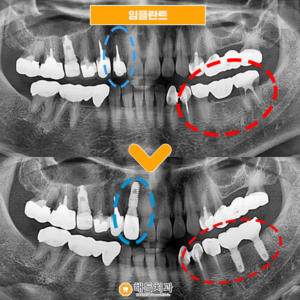

배방역치과 자연치아를 살리기 위해서는 (치료기간 : 2022.03~2022.06) 안녕하세요. 오늘은 저희 배방역치과를 내원하여 임플란트와 치관확장술을 통해 크라운치료하신 환자분을 소개해 드릴까 하는데요. 아래 사진을 보면서 설명해 드리도록 하겠습니다. 배방역치과 위 사진은 고*님의 치아 사진입니다. 고*님은 식사 때마다 통증을 느끼고 불편감을 느낀다고 하여 상담을 원한다고 하셔서 저희 치과에 내원해 주셨는데요, 더보기…